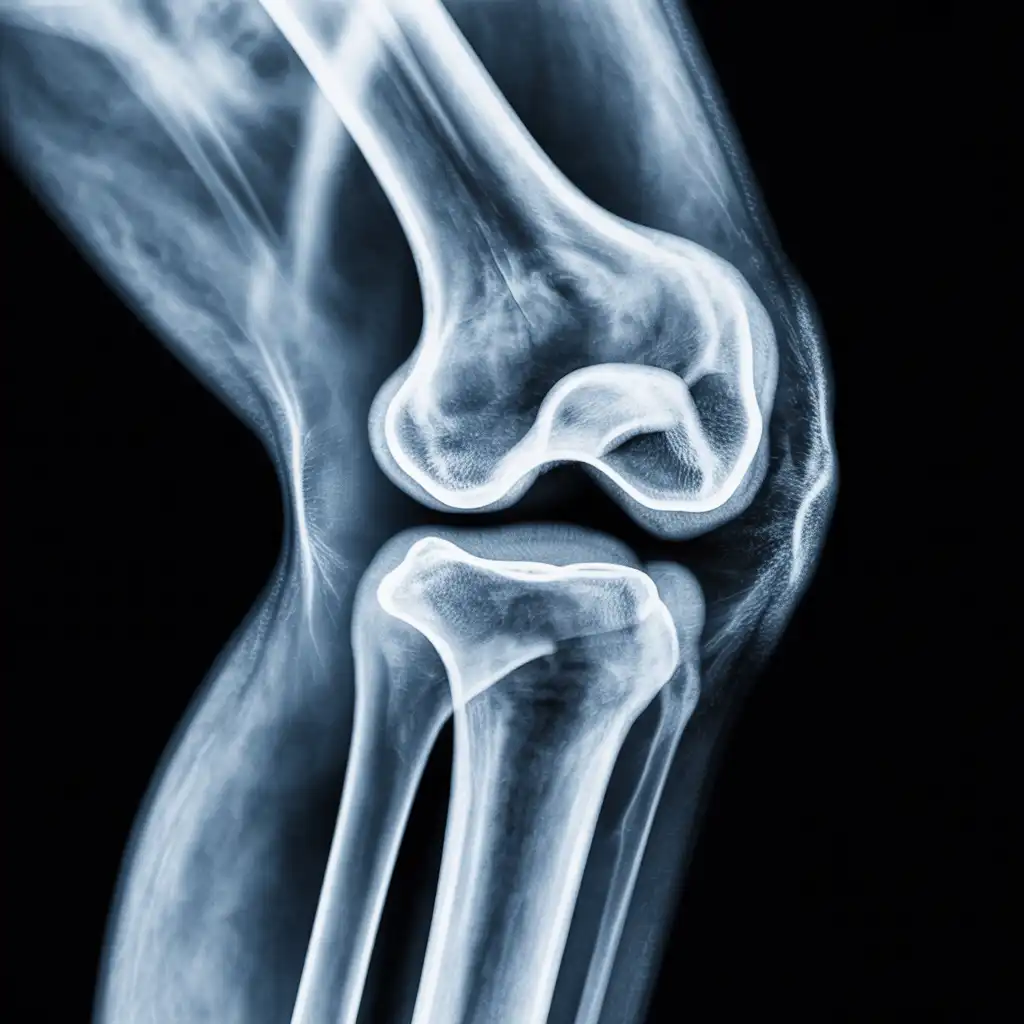

Una radiografia a domicilio è un esame radiologico eseguito da un tecnico specializzato che viene a casa tua con apparecchiature digitali portatili. L’esame si svolge sul posto, senza spostare il paziente e con la stessa qualità di una struttura ospedaliera.

Dopo l’acquisizione delle immagini, queste vengono inviate al medico radiologo che referta rapidamente e ti invia tutto in formato digitale. Un servizio comodo, sicuro e ideale per chi ha difficoltà negli spostamenti.